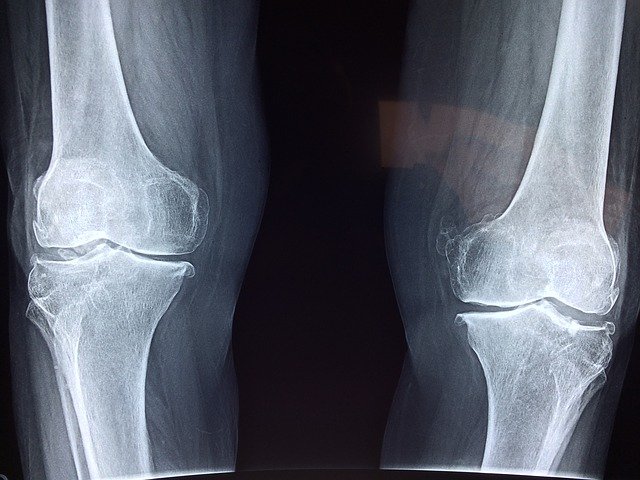

1. 관절염 및 골관절염 완화

MSM은 관절 염증 감소와 유연성 향상에 도움이 된다고 합니다. 한 연구에 따르면 관절염, 무릎 및 허리 통증, 관절 통증 등의 증상을 앓고 있는 사람들이 MSM을 복용하면 이러한 증상들이 완화된다고 합니다. MSM은 신체가 새로운 관절과 근육 조직을 형성하는데 도움이 되는 동시에 관절 부종과 경직을 유발하는 염증 반응을 낮추는데도 도움을 줄 수 있다고 합니다. MSM은 우리 몸의 면역 체계에 도움을 주고 세포 활동을 촉진하는 방식으로 이어지기 때문에 인공적인 치료보다 자연스럽고 효과적인 항염증제라고 합니다.

골관절염 환자 약 120명의 관절 통증에 MSM의 효과를 분석하기 위해 실험을 했는데 MSM 보충제를 약 12동안 꾸준히 섭취한 결과 부기 및 통증, 관절 운동성이 개선된 것으로 나타났습니다. MSM 보충제는 글루코사민과 함께 사용을 한다면 대부분의 사람들에게 부작용 없이 염증과 통증 완화에 도움을 주는 것으로 확인이 됐습니다. MSM 보충제는 관절염에 도움을 주는 훌륭한 자연 치료제라고 합니다.